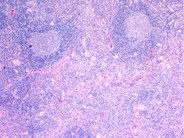

Toxoplasmosis is a common parasitic infection which is usually asymptomatic. Symptoms, when present, are typically those of a flu-like illness with fever, muscle aches, and swollen, tender lymph nodes. Histologically, the involved nodes show follicular hyperplasia and diffuse proliferation of epitheliod histiocytes. The image shown illustrates the follicular hyperplasia and expansion of the interfollicular area by pale appearing cells.